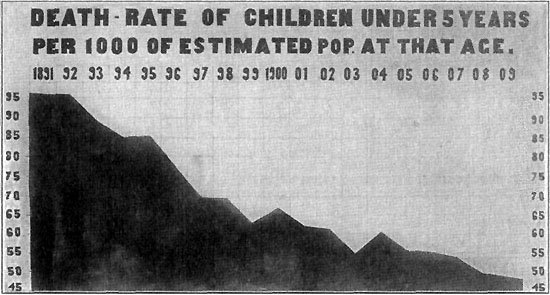

290 The Winning Fight

291 Death-Rate from Measles